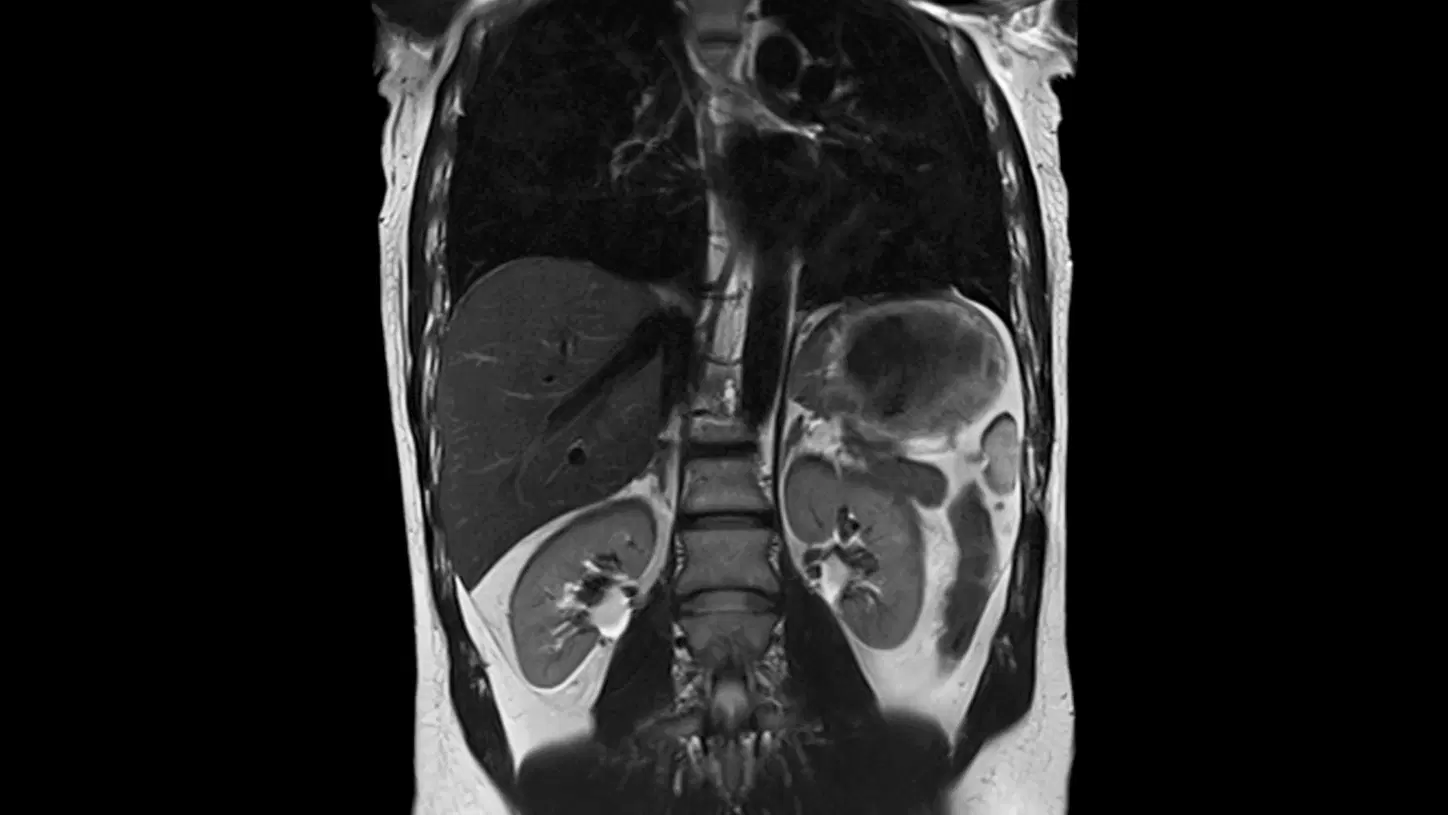

Undoubtedly, finding cancer early increases survival rates. Let’s take kidney cancer for example: it has a 93% 5-year survival rate if detected at stage 0-1 (local), and a 14% 5-year survival rate if detected at stage 4 (distant). That’s a 600% improvement in survival rate for early detection vs. late detection.